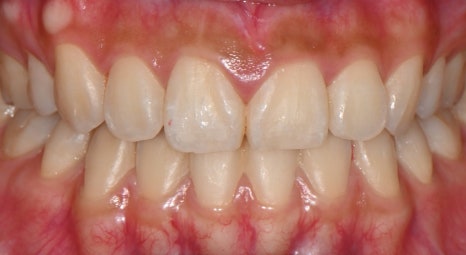

📸 Before

– 어두운 치아 톤

– 살짝 비대칭인 치아 라인